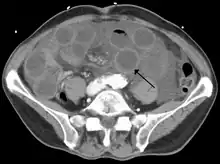

![]() | |

| Computed tomography (CT) showing dilated loops of small bowel with thickened walls (black arrow), findings characteristic of ischemic bowel due to thrombosis of the superior mesenteric vein. | |